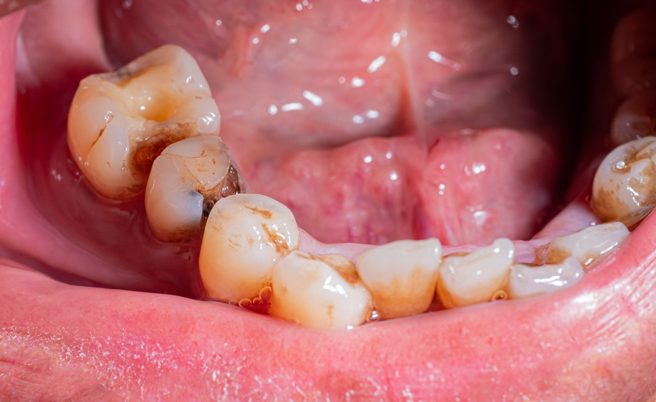

综合陆媒报导,大陆浙江省绍兴市一名22岁女子,因为长时间把可乐当水喝的关系,导致她整口牙齿被腐蚀,除了有许多缺损外,还有多颗牙齿变成黑褐色,甚至只要稍微施力就会脱落,等她痛到难以承受,才前往医院寻求治疗。

医师检查指出,该名女子的状况若想要治疗比较麻烦,光是治疗费初估就要人民币10万元(约新台币44万元)左右,且后续若还需要拔牙、植牙等,总费用恐高达人民币20万元。

医师强调,碳酸性饮料、酸性饮料、果汁等饮品,过度饮用时会引起酸蚀症,对牙齿造成难以抹灭的伤害,最好还是喝白开水就好。